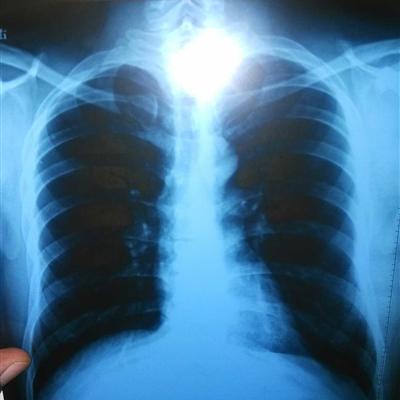

How to treat lung cancer in the elderly?

Patients with lung cancer should go to the hospital regularly for reexamination after treatment. Generally, chest fluoroscopy and liver B-ultrasound examination should be carried out every other month after operation. Later, with the extension of time, the interval of reexamination was gradually extended. Don't avoid medical treatment, take the initiative to go to the hospital for examination when there is a situation, and don't take medicine blindly or eat secret recipes when there is a treatment.